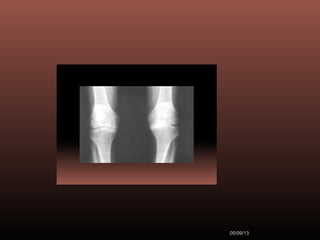

movimentos do quadril direito, sem dor. Tem geno varo

bilateral (fig 2), pequeno derrame no joelho direito,

crepitação em joelhos. Diminuição de flexão em ambos

os joelhos.

Figura ll

Exames Radiográficos

 No início da doença não se observam

anormalidades. Com seu

desenvolvimento, observam-se:

1-Diminuição do espaço intra-articular

2-Esclerose subcondral (eburnação)

3-Osteófitos;

4-Erosão e anquilose óssea

(pseudocistos ósseos).